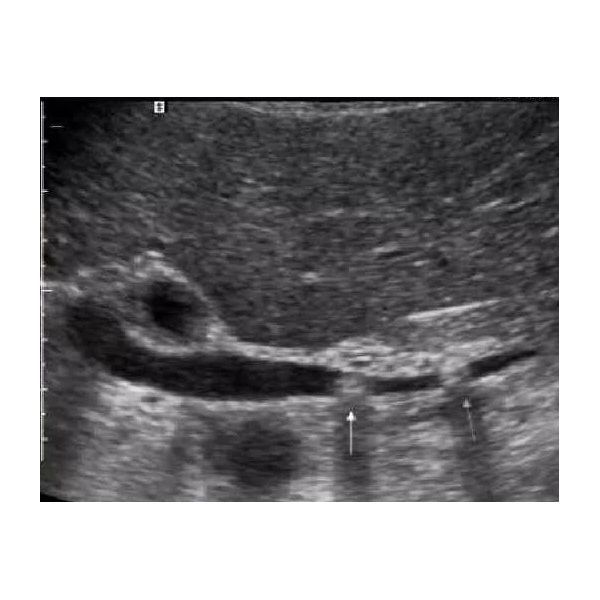

По результатам ультразвукового исследования (УЗИ) органов брюшной полости выявлены:

- уплотнение паренхимы (основной ткани) печени;

- желчнокаменная болезнь;

- увеличение желчного пузыря и конкременты (камни) диаметром 1–2 см;

- диффузные изменения поджелудочной железы (т. е. во всей её структуре);

- отсутствие свободной жидкости в брюшной полости.